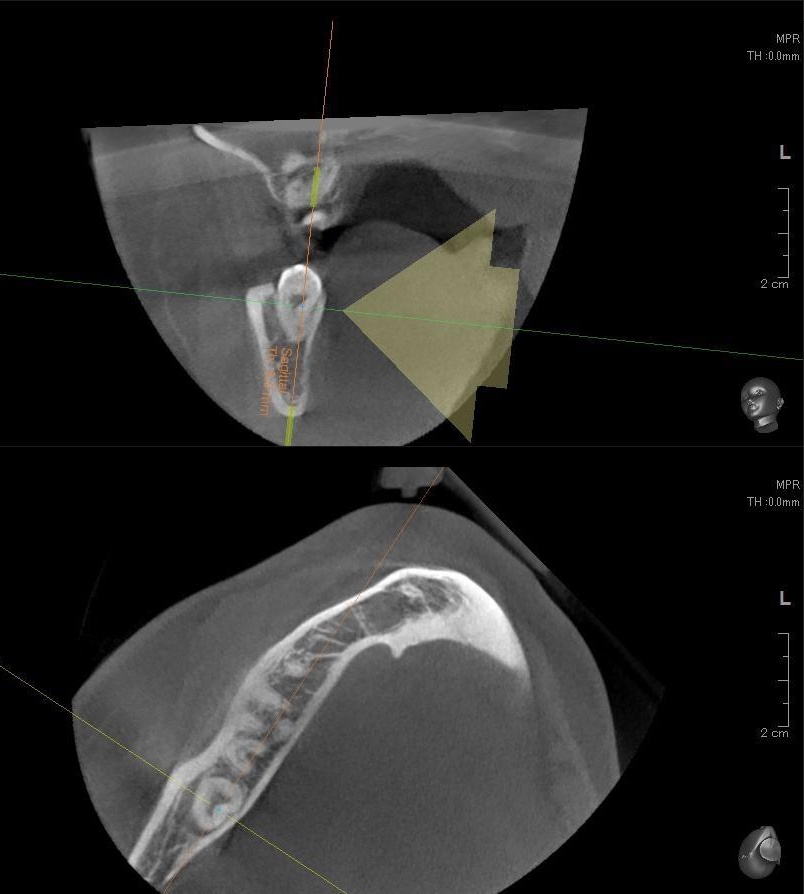

さらに、下顎の親知らずは下歯槽神経に非常に近いところに生えている場合もあるため、CTも撮影し詳しい解析を行います。

親知らずが生えている位置が、神経に近い、あるいは神経に当たっている場合は、大きな病院に紹介する場合もあります。

親知らずの根っこは下歯槽神経から近い距離にありますが、抜歯は可能との診断でした。